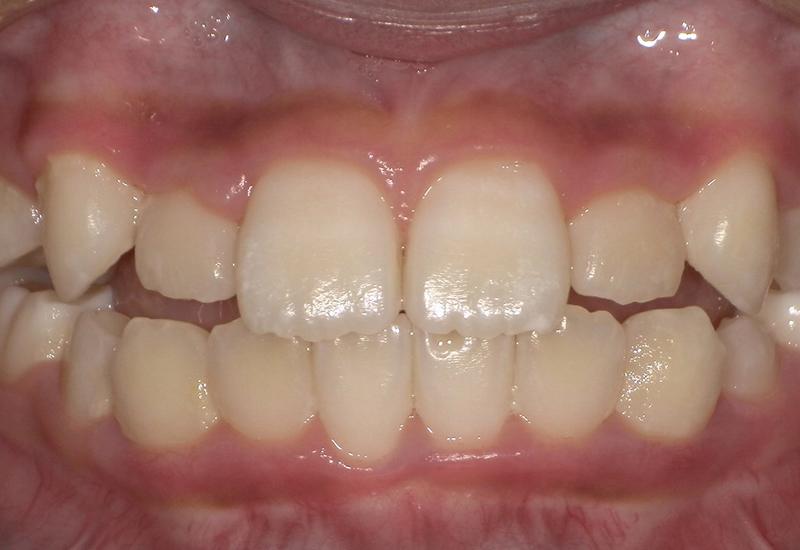

症例② シェイプメモリーアライナーによる混合歯列期の矯正

治療期間 6ヶ月

治療時の年齢/性別 10歳 / 女性

かかった治療費 440,000円

治療方法 シェイプメモリーアライナー

注意点・リスク 今、現在萌えてきている永久歯を動かす為、なるべく早く治療を終了させる